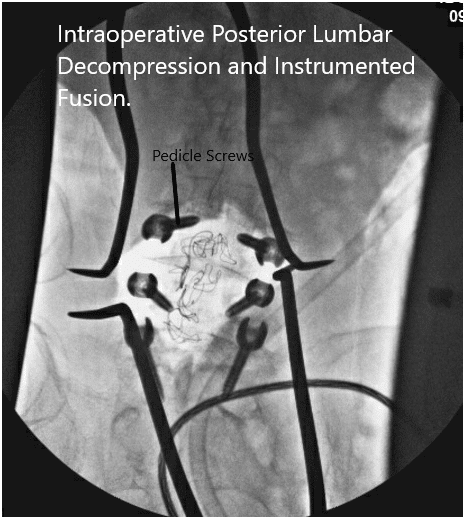

Intraoperative fluoroscopy images.

Now the pedicle screws for the S1 were planned and the pedicle of S1 was probed from either side and checked under C-arm. After finding an acceptable position. The pedicle screw of 6 mm x 45 mm cortical fix screw was put on both pedicles of S1.

The pedicles of L5 were cannulated now and the position of the probe was checked under the C-arm and found to be acceptable and biopsy material was sucked out using a Jamshidi needle from the right pedicle of LS. Some tissue and bone marrow aspirate was sent for biopsy. A 6 mm x 40 mm cortical fix screw was inserted on both pedicles of L5.

The pedicles of L4 were cannulated similarly and checked under C-arm and found to be acceptable. A 6 mm x 45 mm cortical fix screw was inserted on both pedicles of L4. The screw heads were lined well on both sides. The wound was washed copiously with normal saline mixed with Bacitracin and gentamicin.

The screws were lined and rods were placed on both sides and tightened to the screw heads. The final pictures of the screw were taken with C-arm and saved. Hemostasis was achieved. Vancomycin antibiotic was sprinkled into the wound. Considering the durotomy a deep suction drain was not put. The closure was done in layers. Two suprafascial drains were put. The counts were completed, checked, and correct at the end of the procedure. The patient was transferred into a supine position on the bed, extubated, and moved to the postoperative care unit in a stable condition.